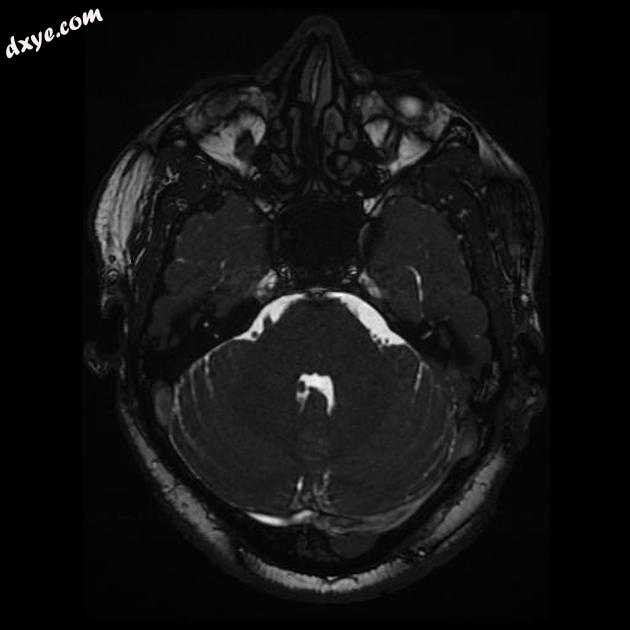

Coronal T2

MRI 序列显示右侧颈内动脉的部分血栓囊状动脉瘤位于 C6/7 节段的交界处,大小为 11 x 7 毫米,颈部为 2.5 毫米,压迫动眼神经 (III) 的相邻节段,在 T1 上清晰可见和 FIESTA 序列。

位于 C6/7 交界处的右侧颈内动脉部分血栓囊状动脉瘤的 MRI 特征,压迫同侧动眼神经 (III)。